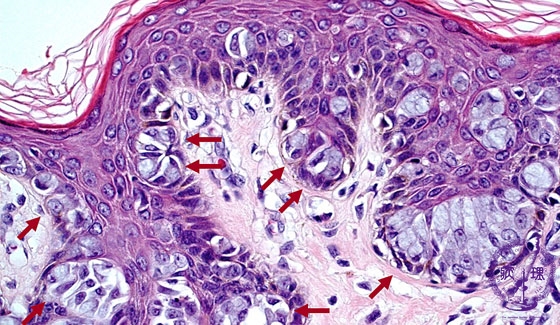

- 14.Breast

- (9)Paget’s disease

Microscopic image(HE stain, high power view):Paget cells can be detected in the full thickness of the skin, but with a strong tendancy to stay within the epidermis. The large nuclei of Paget cells with prominent nucleoli, often pushed aside by intracellular mucous.